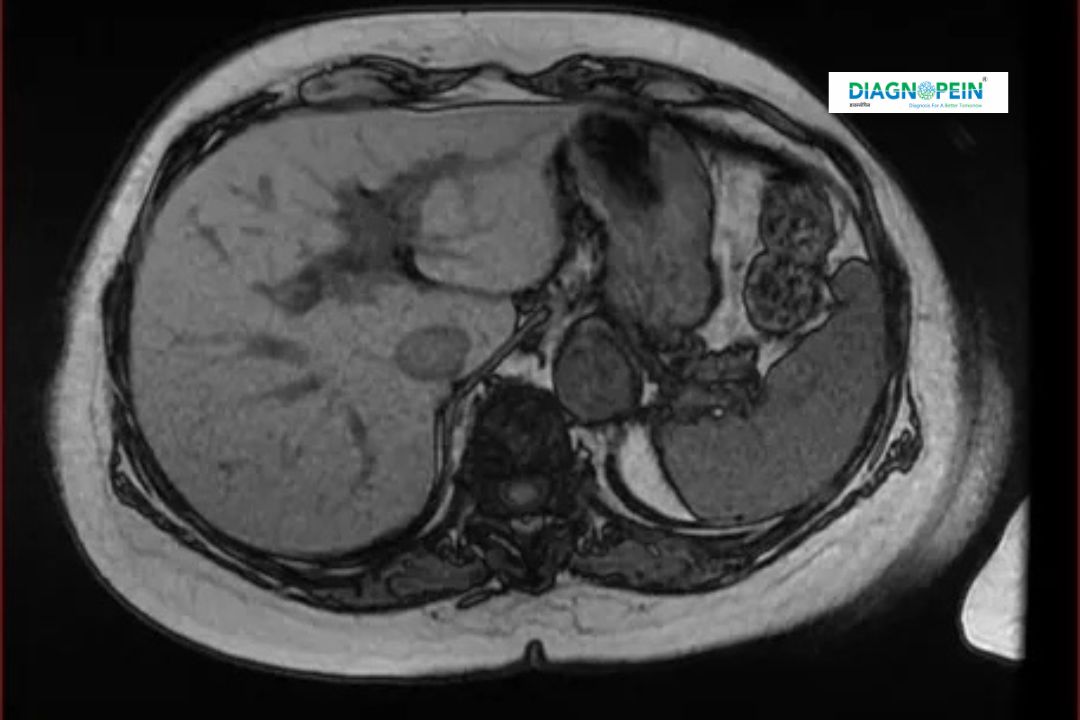

MRI Abdomen and Pelvis is a non-invasive imaging test that uses powerful magnetic fields and radio waves to generate detailed cross-sectional images of the abdominal and pelvic region. It helps in visualizing the internal organs including the liver, kidneys, pancreas, spleen, bladder, uterus, and prostate without the use of X-rays.

At Diagnopein, Nanded, MRI Abdomen and Pelvis is performed using advanced MRI scanners that deliver high-resolution images, enabling accurate diagnosis